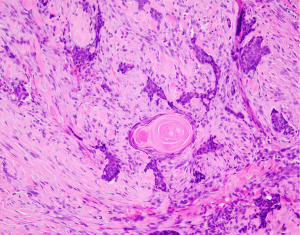

To distinguish the tumor of the parotid gland from the possible metastasis from BCC of the left medial canthal region previous histopathological slides were also reexamined and compared with histopathological examination of the removed parotid gland tumor. In histopathological examination, high similarity, almost identical morphology and antigenic expression of the right parotid gland tumor and previously excised BCC of the left eyelid was described. p40, p63 and Ep-Cam staining performed on the right parotid gland tumor and BCC of the left eyelid showed an identical, strong expression of all the antigens mentioned above. The Ki-67 labeling index in the right salivary gland tumor was about 60%, and in the BCC of the left eyelid was higher (80% to even 90%). The labeled nuclei were not limited to the basal layer of cell nests, but were equally distributed in the cancer foci which is an essential feature for differentiating between squamous cell carcinoma and basaloid squamous cell carcinoma. In our case p40, p63 and Ep-Cam staining were applied to differentiate squamous cell carcinoma from basaloid carcinoma and the result confirmed the basaloid nature of squamous cell carcinoma (Figure 2).